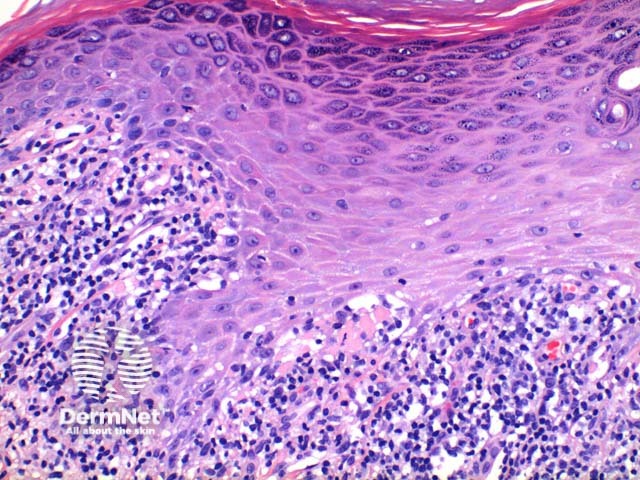

Scanning power view of lichen planus shows a lichenoid reaction pattern (Figure 1) characterised by the combination of degeneration of the basal layer of the epidermis and a band like lymphocytic infiltrate obscuring the dermoepidermal junction. There is irregular epidermal hyperplasia forming a characteristic saw-tooth appearance with wedge-shaped hypergranulosis (Figures 1 and 2). The basal layer of the epidermis exhibits vacuolar degeneration with typically prominent necrosis of individual keratinocytes (Figure 3). The inflammatory infiltrate is chiefly lymphocytic and forms a dense band in the superficial dermis (Figure 4).

Figure 2